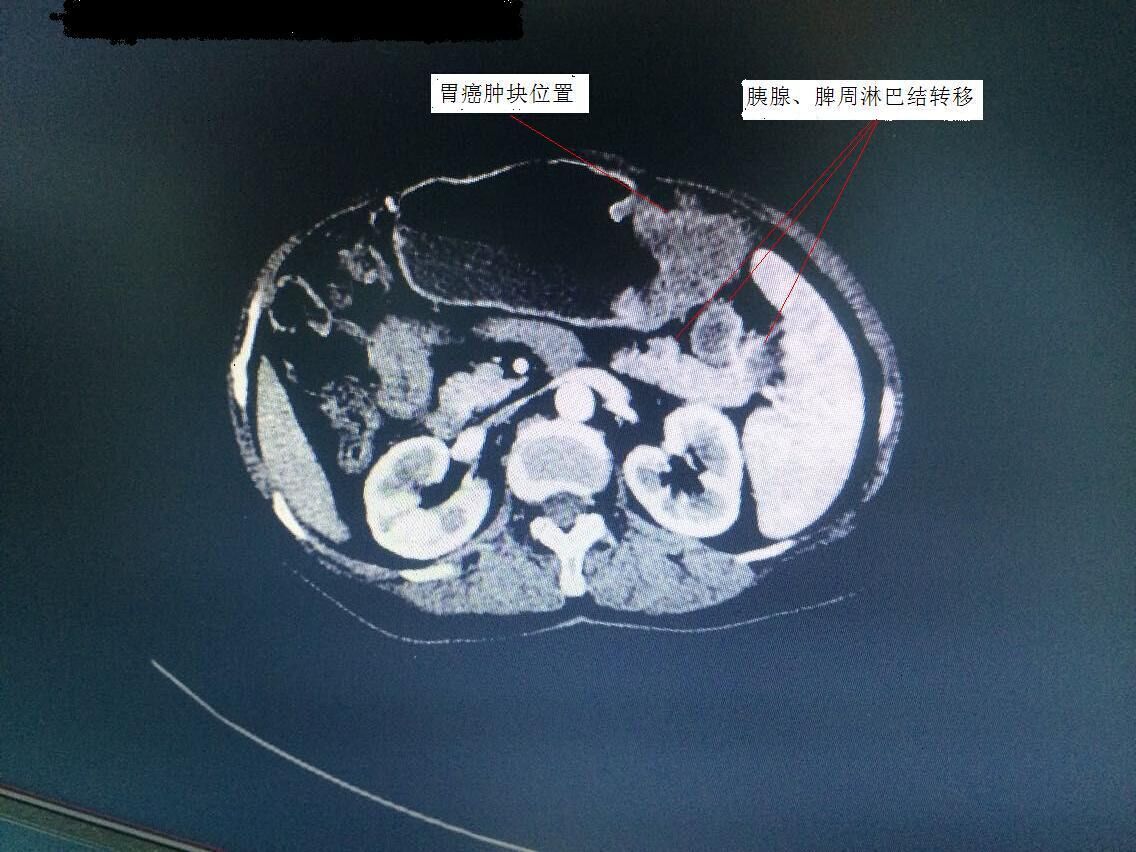

胃腸外科譚曙光主任率領(lǐng)科室團(tuán)隊(duì),術(shù)前對(duì)手術(shù)方案進(jìn)行了仔細(xì)研究。該患者胃癌腫塊位于胃體,腫塊較大,且胰腺尾部、脾門等周圍淋巴結(jié)轉(zhuǎn)移(見圖1)。為保證治療效果,提高患者生存質(zhì)量,需行全胃、胰腺體尾部以及脾臟聯(lián)合切除。此等手術(shù)在以往傳統(tǒng)開腹方面均具有較高難度,若想在微創(chuàng)下完成切除,更是難上加難。經(jīng)過科室嚴(yán)密的探討,最終確定為該患者行腹腔鏡下微創(chuàng)手術(shù)。手術(shù)歷時(shí)3個(gè)小時(shí),在手術(shù)室及麻醉科的配合下,順利完成衡陽(yáng)市第一例腹腔鏡下胃癌根治聯(lián)合脾臟、胰腺體尾部切除術(shù)(術(shù)后標(biāo)本見圖2)。術(shù)后,該患者恢復(fù)良好,手術(shù)疤痕不到傳統(tǒng)手術(shù)的四分之一(見圖3),目前已開始術(shù)后化療。

圖1